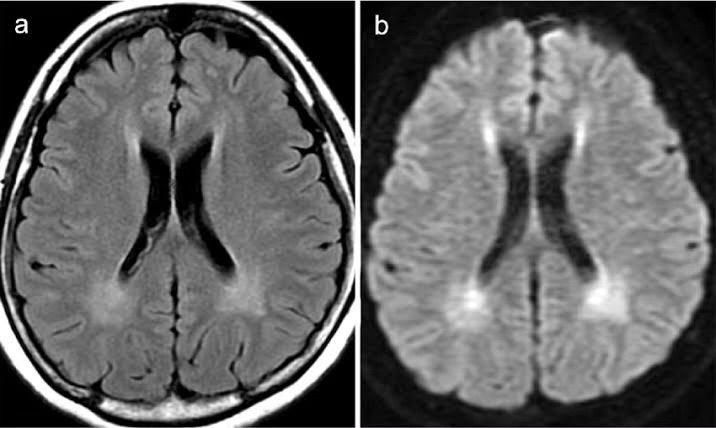

A 32-Year-Old, Female Patient with Phenylketonuria (PKU). A Flair Image... | Download Scientific Diagram, Accessed 14 Aug. 2024.